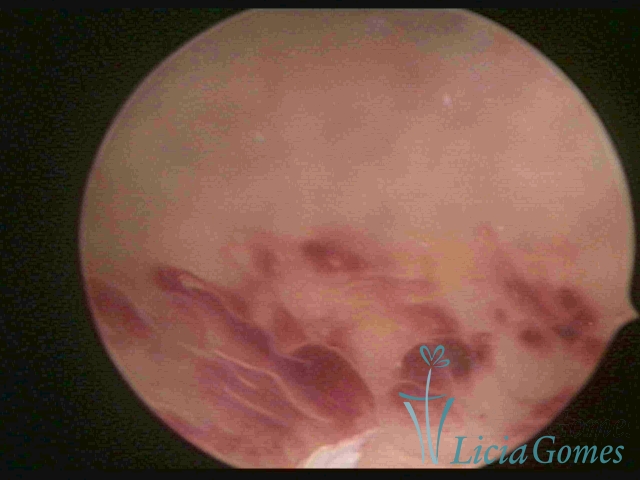

CHRONIC ENDOMETRITIS

The surface of the endometrium may present changes such as a red punctuate forming vascular balls, a smooth, hypervascularized endometrium or intensely presenting red areas, with accurate edges and yellowish white spots in its interior, providing a "STRAWBERRY PEEL" aspect, a pale yellow color of fundic and lateral commissures, in contrast with the intense red color present in the walls.